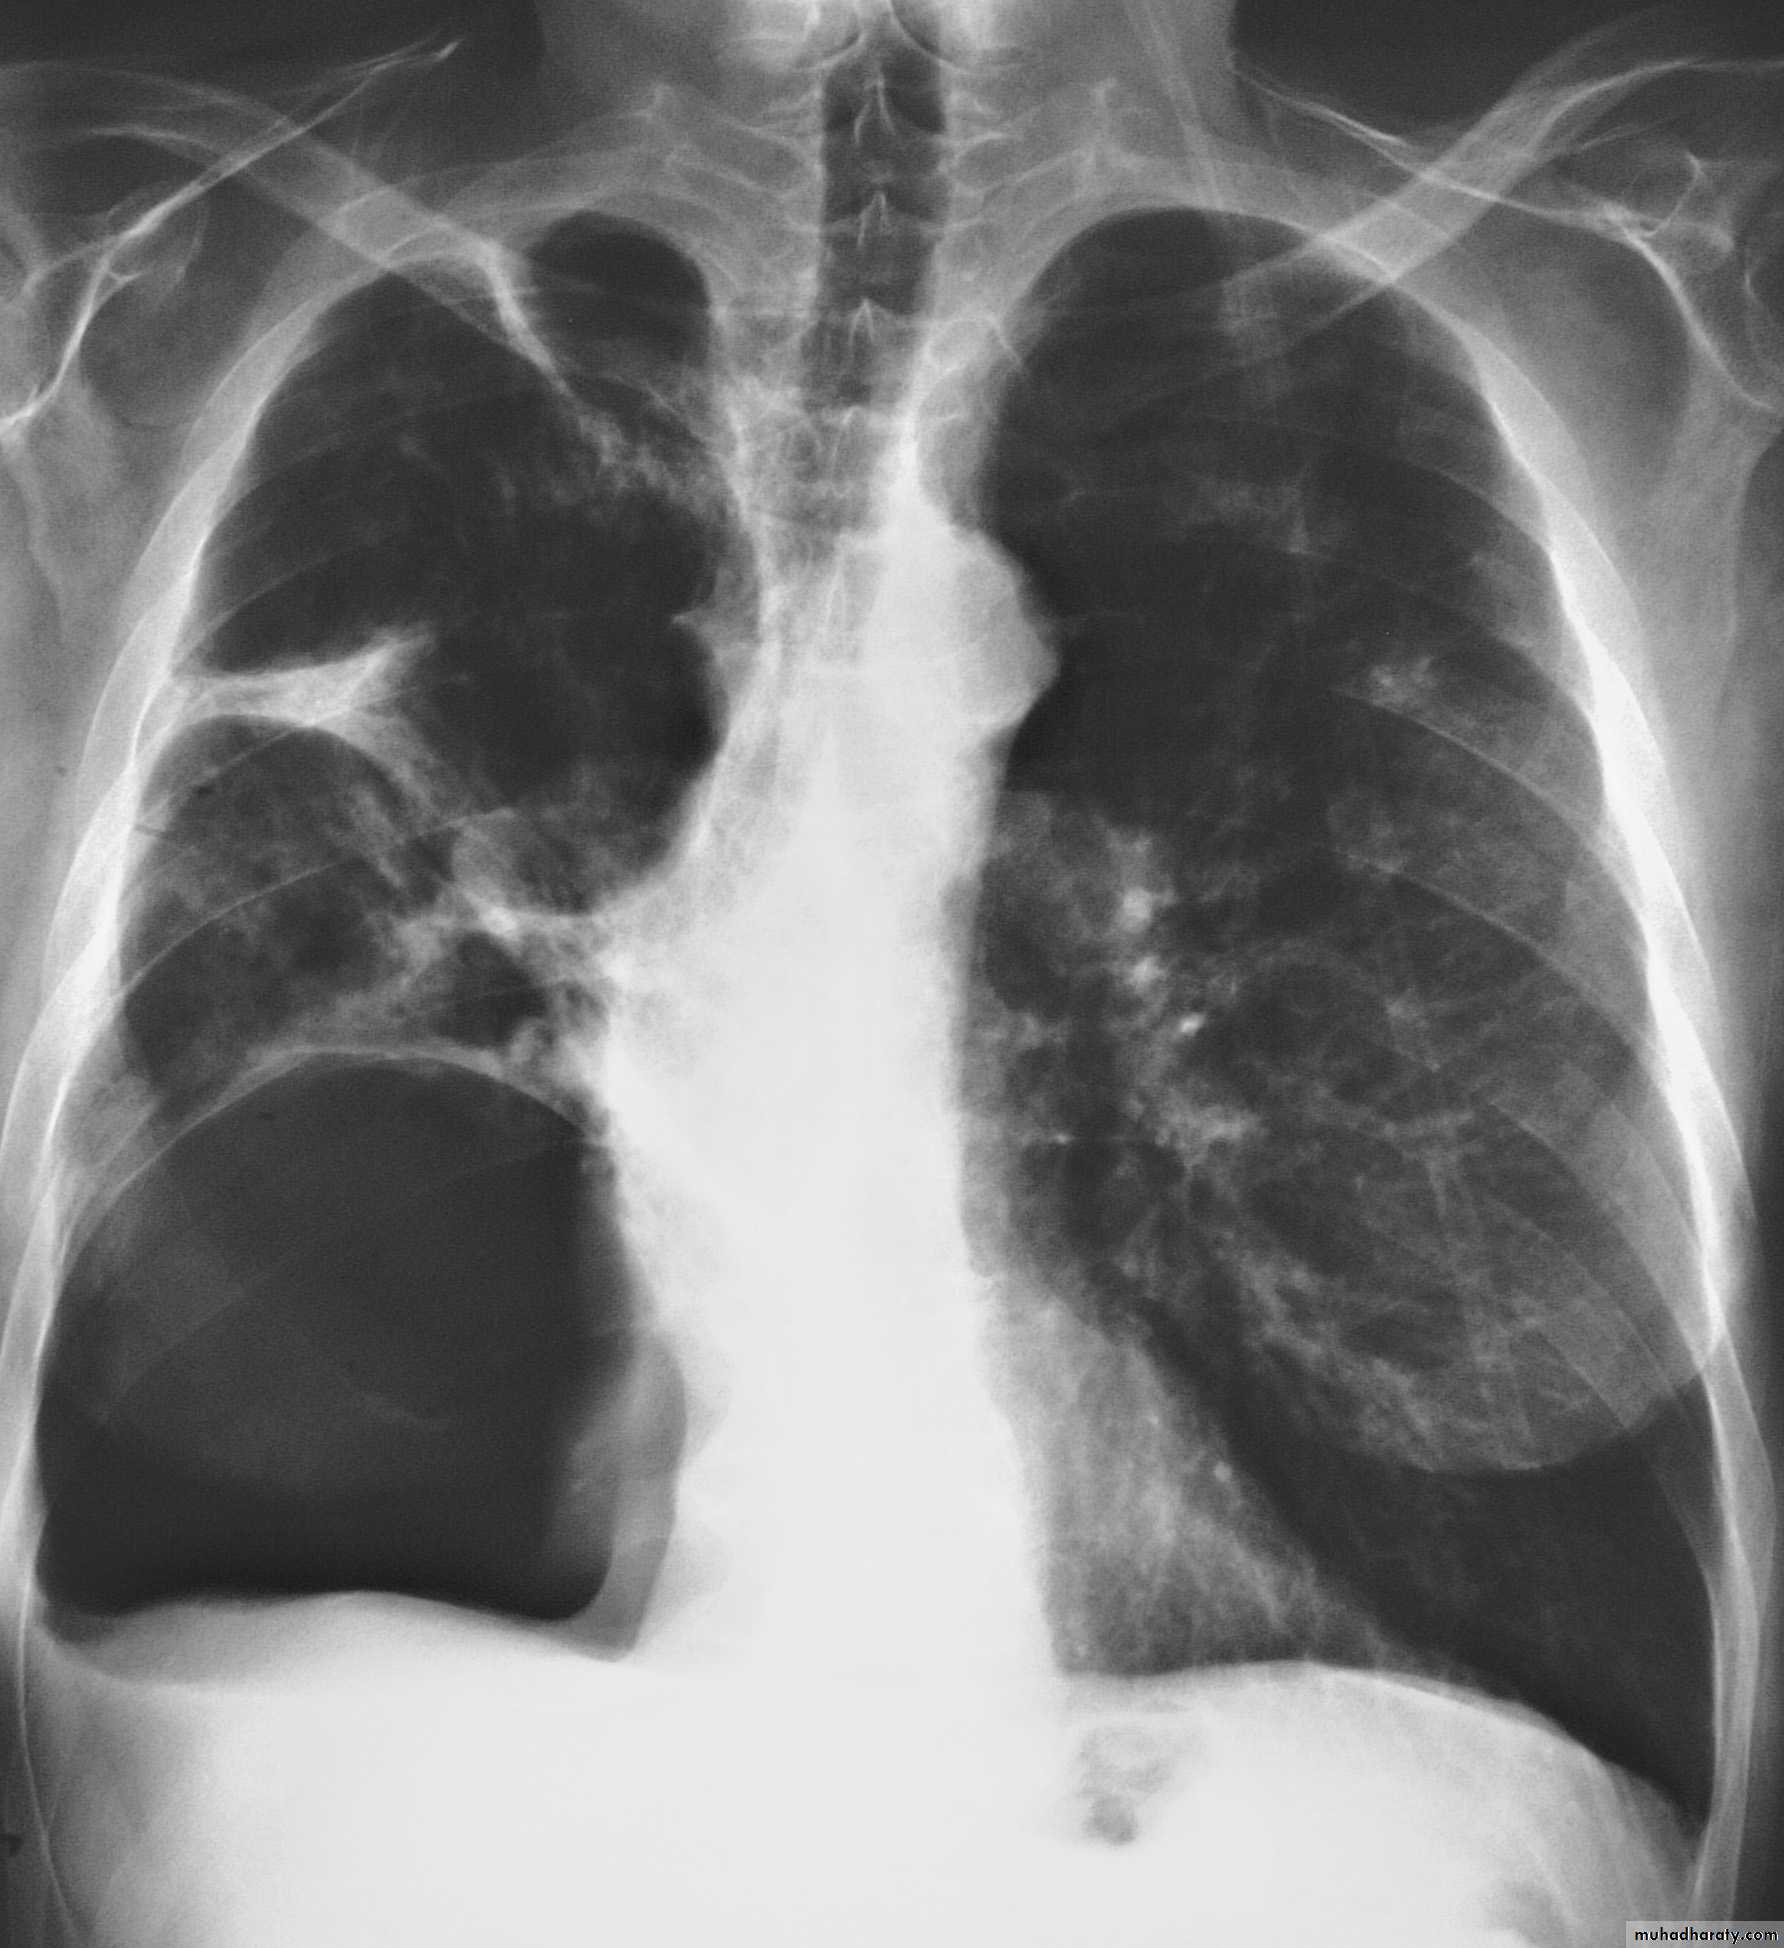

Chest X-ray;Shows the sharply defined edge of the deflated lung with complete translucency (no lung markings) between this and the chest wall. Chest X-rays also show the extent of any mediastinal displacement and give information regarding the presence or absence of pleural fluid and underlying pulmonary disease.